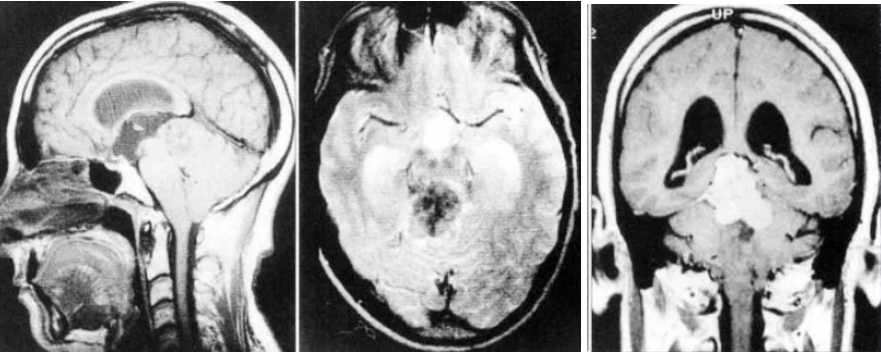

Иллюстрации и пояснения: гиподенсивный очаг на КТ головного мозга